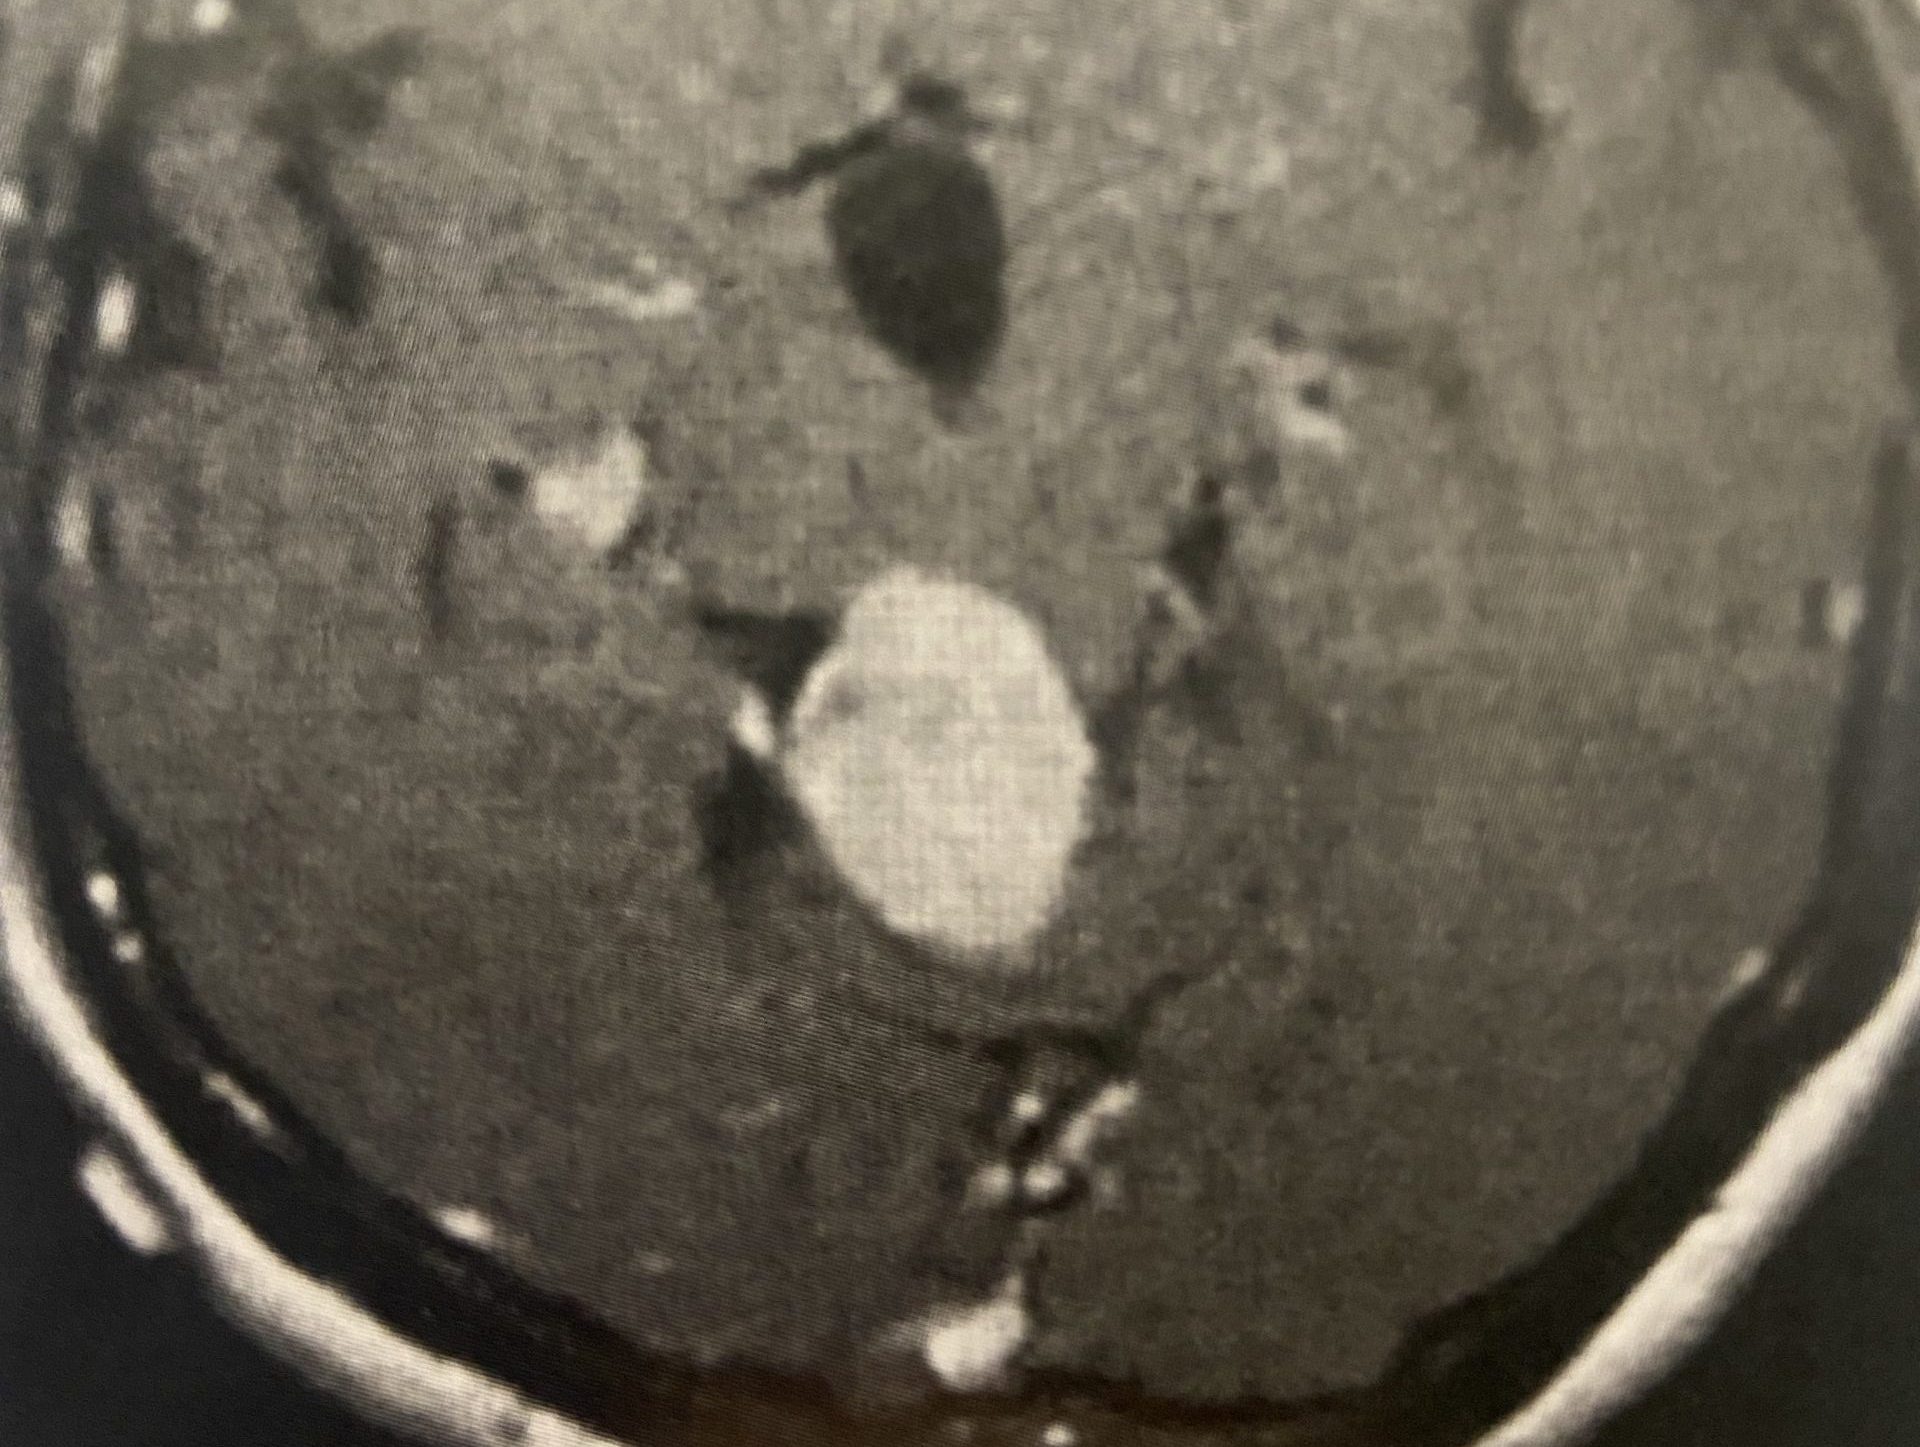

(Fig. 2) Axial T2 cervical MRI at C4-5 demonstrating significant osteophytic disease with bilateral neural foraminal compression of the C5 nerve roots, right greater than left.